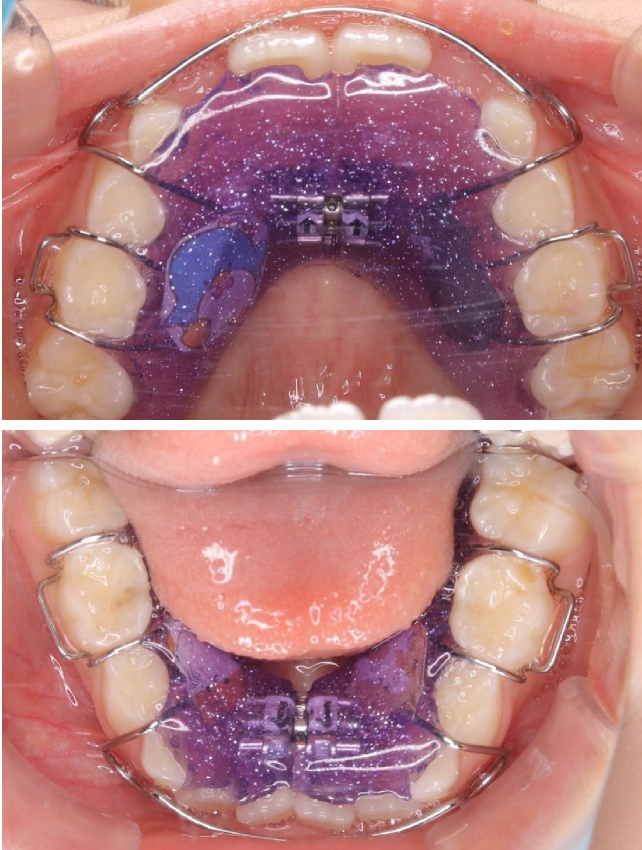

1期治療で使用する装置

-

拡大床

- 機能

- 横に広げるための装置

- 期間

- 6か月~10か月程度

成長期のお子さまの顎をゆっくりと広げる矯正装置です。顎の成長を正しい方向へ導くことで、歯がきれいに並ぶための土台を整えます。歯を無理に動かすのではなく、顎の成長を活かした治療のため、痛みが少なく、お子さまへの負担が比較的軽いのが特徴です。

拡大床は、多くの場合1期治療の中心となる装置で、将来的な本格矯正の必要性を減らすことにもつながります。 -